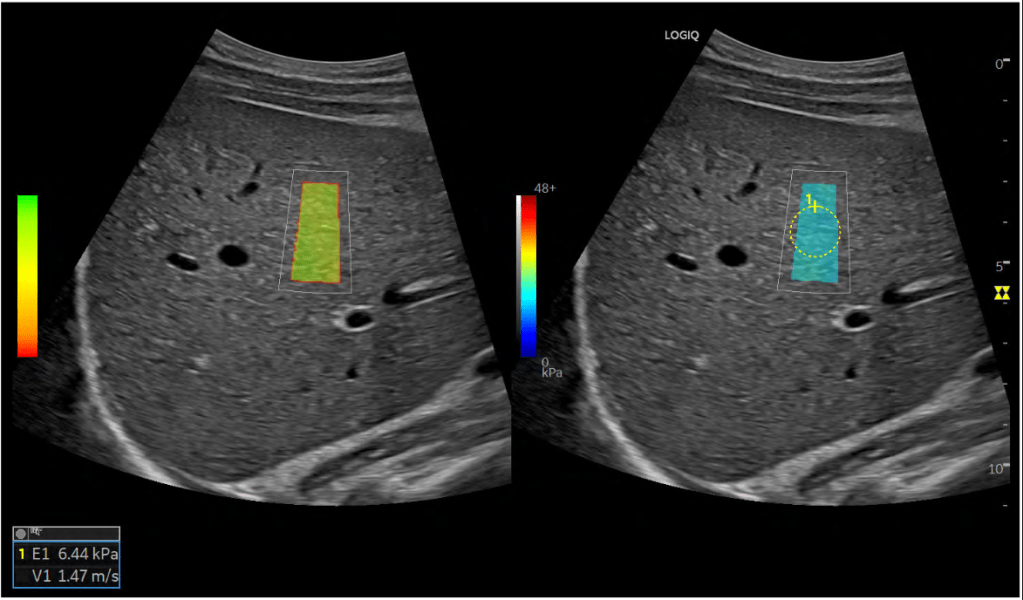

A elastografia hepática por ultrassom é um exame que permite estimar o grau de fibrose do fígado de forma segura, confiável e acessível. Essa estimativa é útil para avaliar o estágio de doenças crônicas do fígado, definir necessidade e opções de tratamento e diagnosticar cirrose em seu estágio mais inicial.